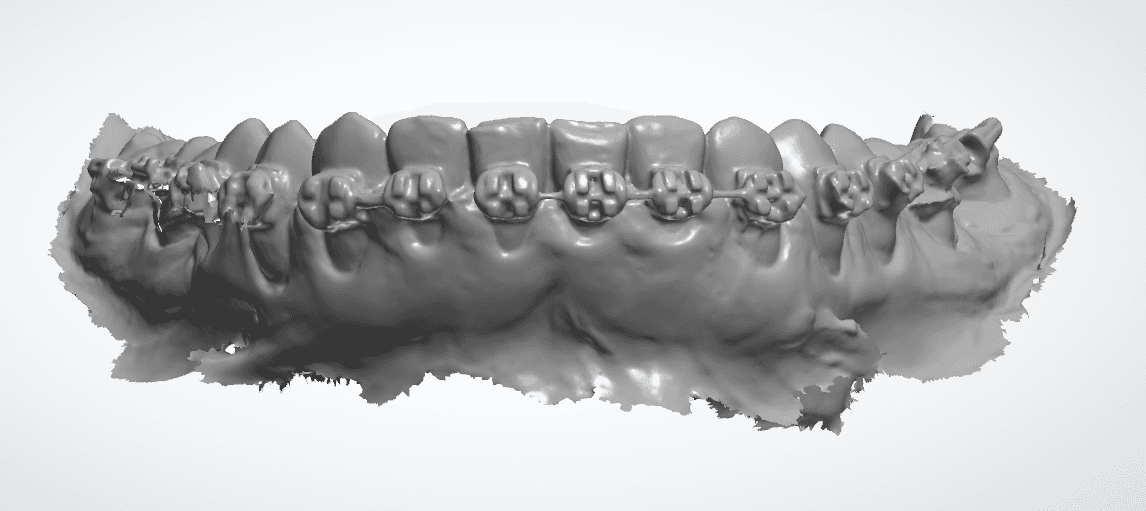

Falha de “Costura”

O escaner funciona tirando varias fotos da boca e vai “costurando” uma com a outra, formando uma imagem 3D, como se estivesse tecendo uma malha de tecido, tanto que é muito comum usar o termo “Malha” para se referir a um escaneamento 3D.

É muito comum você ter um defeito nessa junção da malha vestibular e lingual nas incisais Bateria Labial (tanto superior quanto inferior), esse defeito também conhecido como “falha de costura”.

Apesar de parecer um defeito pequeno ele pode prejudicar a adaptação do alinhador fatalmente por um lado da boca não ter alinhamento com o outro.